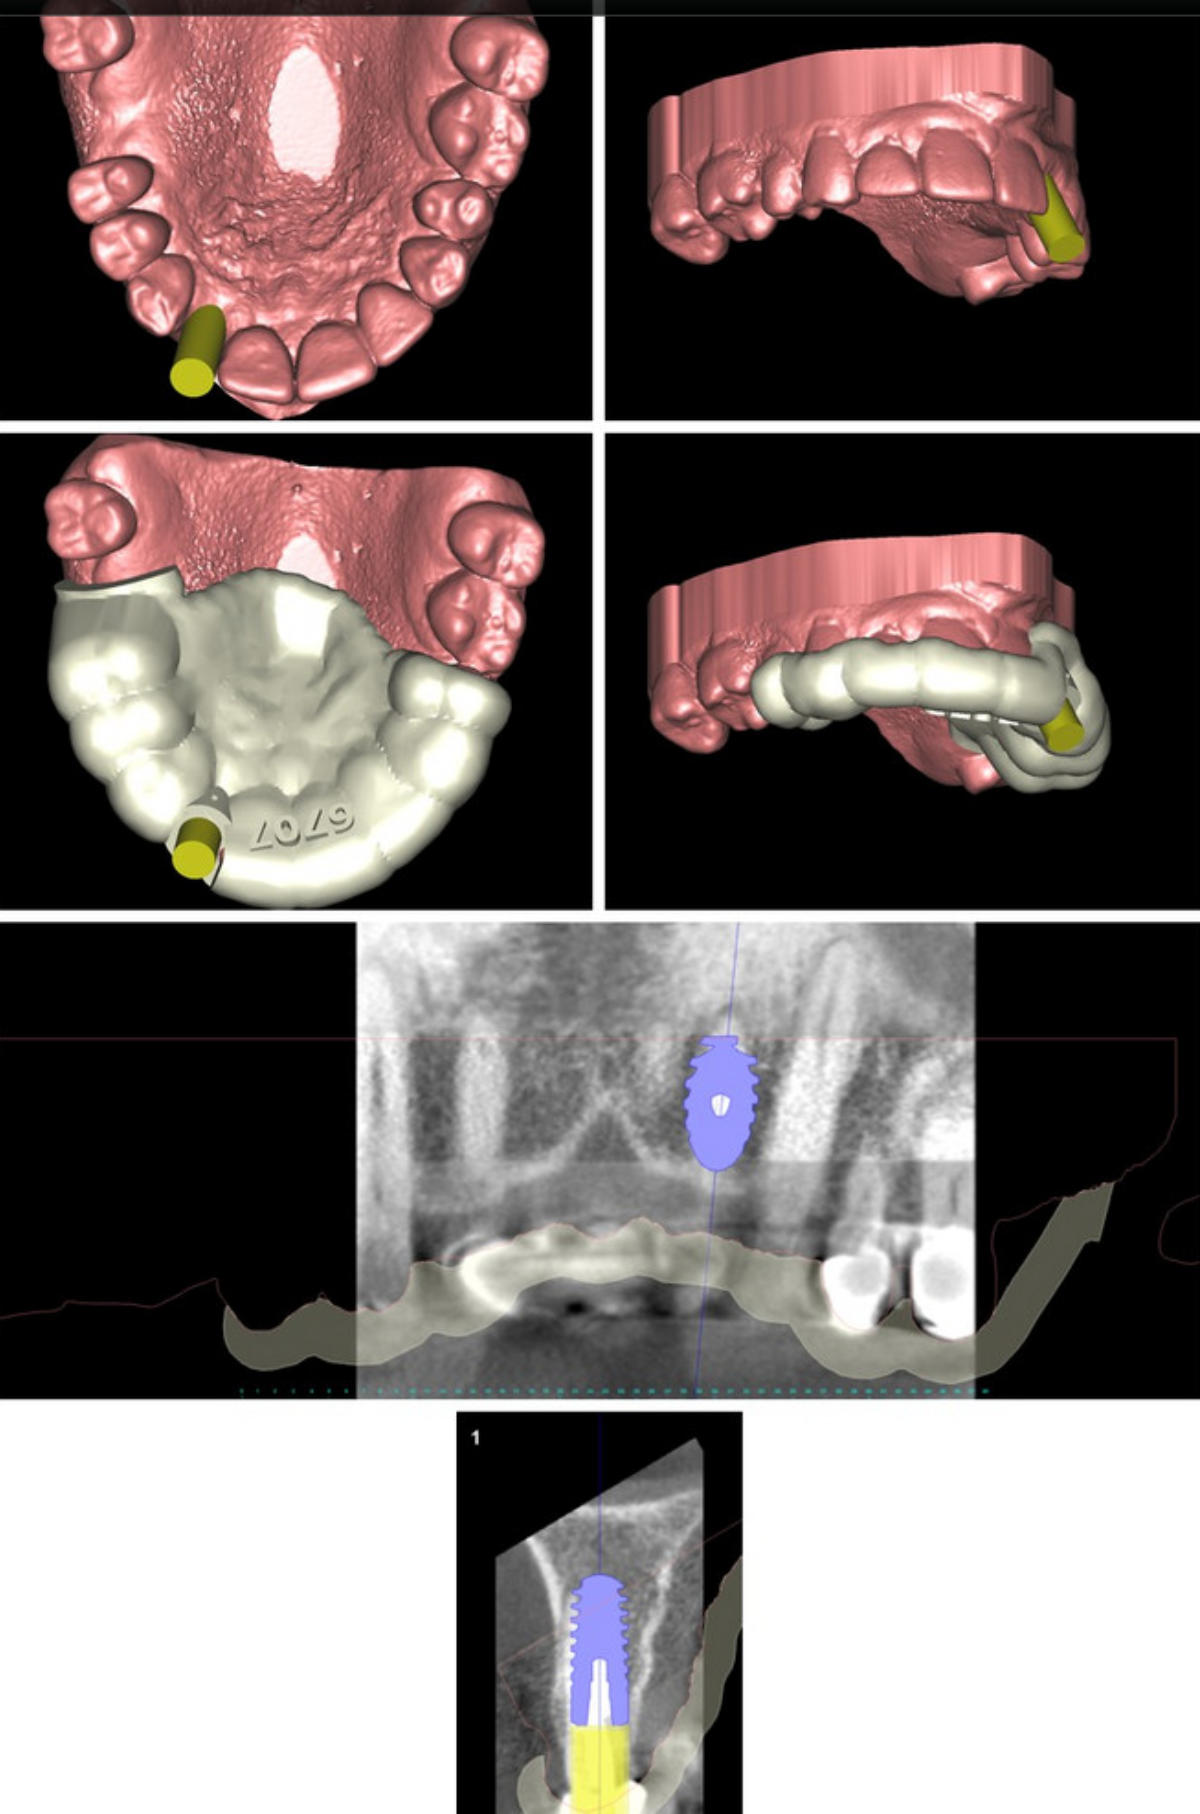

An Hand von vorliegenden dreidimensionalen Befunddaten ( 3D- Röntgenbild -DVT/ digitalisiertes Kiefermodell) wird vor dem eigentlichen Eingriff am Computer mit einer speziellen Software eine virtuelle Implantation durchgeführt ( Simulation der geplanten Operation) und auf Basis der ermittelten Daten eine Bohrschablone für das Setzen der späteren Implanate in Auftrag gegeben. Vorteile des Verfahrens sind : klinische Umsetzung und Reproduzierbarkeit der gewünschten Implantatpositionen Ermittlung des eventuell erforderlichen Bedarfs an knochenaufbauenden (augmentativen) Maßnahmen maximale Schonung benachbarter anatomischer Strukturen vor unbeabsichtigter Verletzung (Nachbarzähne, im Operationsgebiet verlaufende Nerven, Kieferhöhle etc.) Umsetzung der in der virtuellen Planung in funktioneller und ästhetischer Sicht als optimal ermittelten Implantatposition ; die individuelle intraoperative Korrekturmöglichkeit bleibt jeder- zeit gegeben Verkürzung des operativen Eingriffs durch die präoperative Operationsplanung

umfangreiche virtuelle Operationsplanung 3-D Implantatplanung Operationsschablone - angefertigt  nach virtueller Implantation umfangreiche virtuelle Operationsplanung umfangreiche virtuelle Operationsplanung

Virtuelle Implantation (Operationsplanung) am Computer